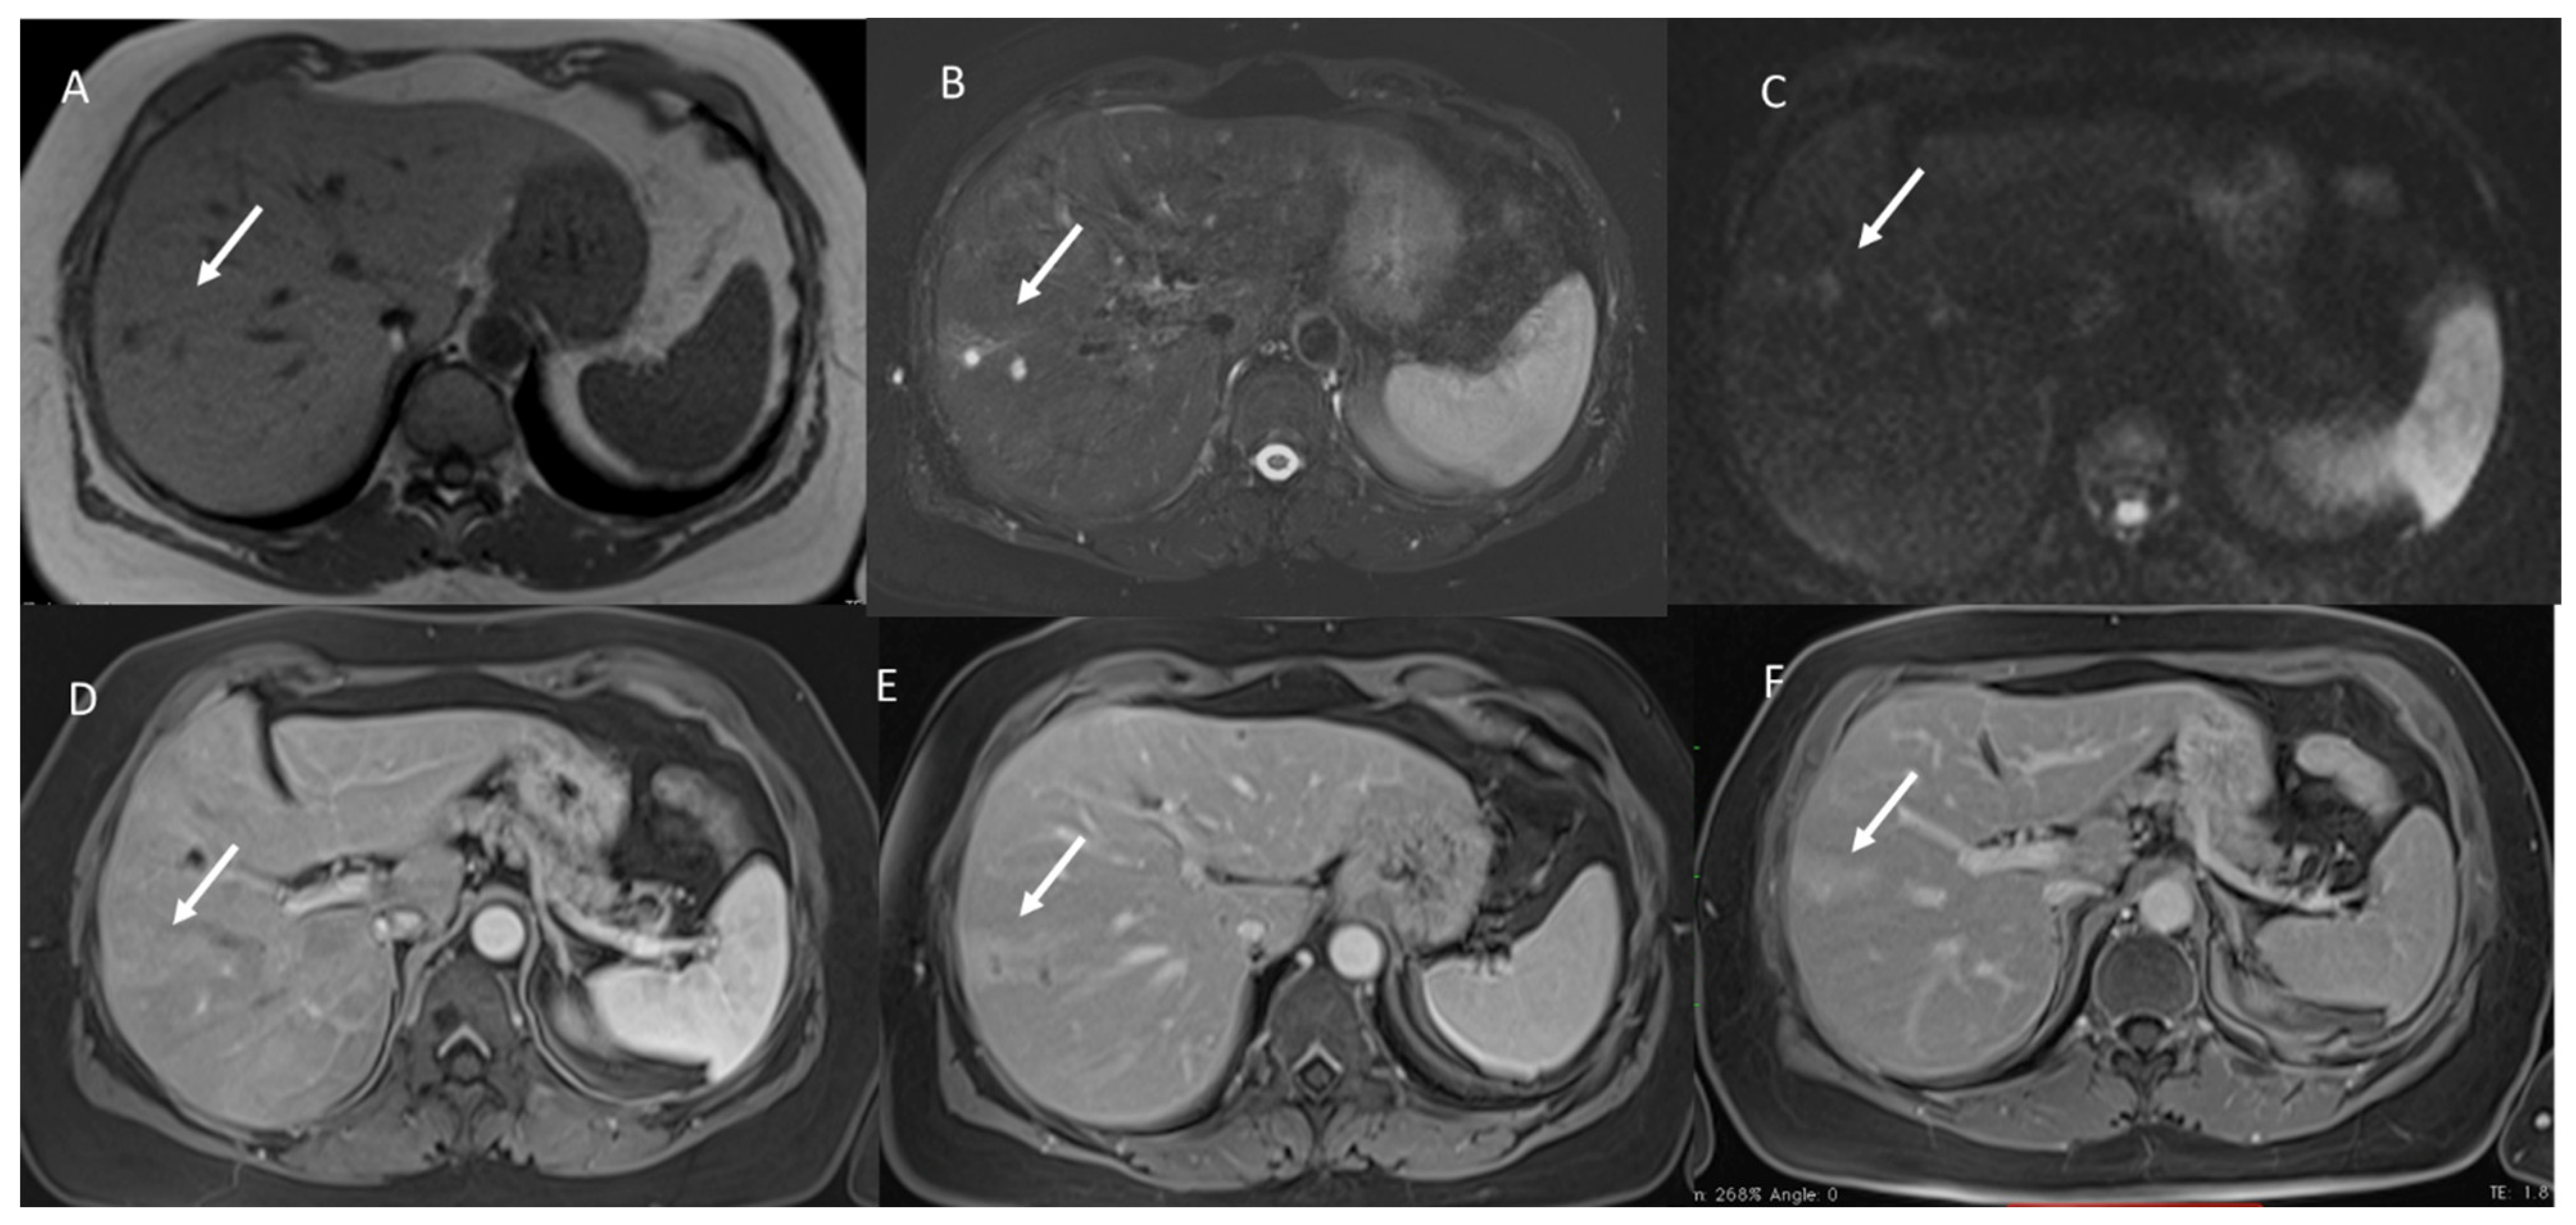

- The signal intensity (SI) in T1 W, in T2-W, DWI sequences and the apparent diffusion coefficient (ADC) map.

3.2. T2-W Signal Intensity and Diffusion

3.3. Arterial Phase Appearance

3.4. Portal Phase Appearance

3.5. Equilibrium Phase Appearance